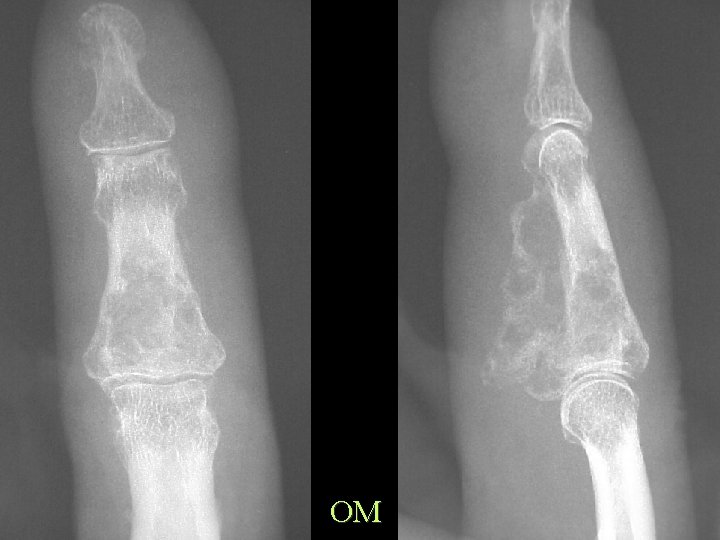

OM

Exclude underlying bone disease